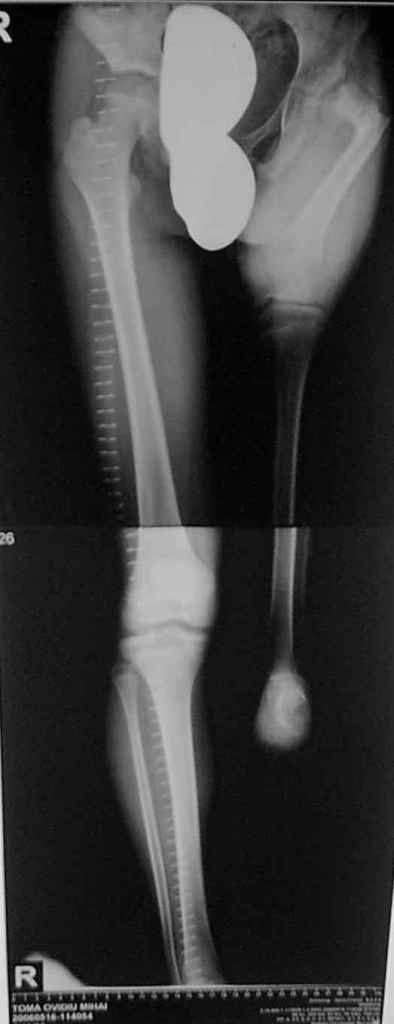

Извините за задержку(по техническим обстоятельствам) еще просим извинения за ошибки (трудный перевод). Больной с врожденной гипоплазией проксимальной части бедра, с ацетабулярной дисплазией. В 6 лет первая операция по стабилизации тазобедренного сустава прилагаю Рг. К нам обратился в следующей ситуацией:укорочение на 26см нижней конечности, соха flecta - 45 °.подвижной до 100°, genu flexum 25-30° мобильный до 90°. Активность мышц бедра- очень слабое, мышцы голени и сама голень отстающей в развитии. В настоящее время пациент ходит самостоятельно с протезом. Спасибо всем еще раз за присланные варианты лечения.Rx при рождении:ниже

Rx на сегодняшнии день